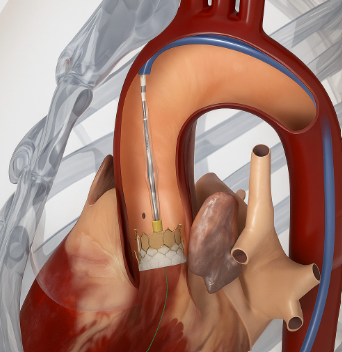

Mumbai: Edwards Lifesciences, a global leader in structural heart innovations, has announced the launch of its next-generation transcatheter heart valve platform in India, marking a significant milestone in the treatment of aortic stenosis.

This advanced therapy is designed to meet the needs of patients who are not candidates for open-heart surgery, offering a durable, minimally invasive solution that supports long-term health and quality of life.

Edwards’ latest-generation balloon-expandable transcatheter heart valve incorporates a proprietary calcification-resistant tissue technology that helps prevent calcium buildup on the valve leaflets, which is a primary cause of structural valve deterioration and the need for reintervention. The valve also features dry tissue storage, simplifying hospital workflows, and a taller, textured outer sealing skirt to reduce paravalvular leak.4,5

Central to Edwards’ approach is its ‘lifetime management’ principle, which prioritises comprehensive planning of a patient’s treatment journey from the initial procedure. A key component is the valve-in-valve technique, which enables the placement of a new transcatheter valve within an existing transcatheter valve or a degenerated surgical valve, should degeneration occur years later. This approach maintains a minimally invasive pathway and reduces the need for repeat open-heart surgery in patients requiring future interventions.Commenting on the Edwards’ next-generation transcatheter heart valve platform, reputed cardiologists from India shared their perspectives. Dr. Ravinder Singh Rao, Interventional Cardiologist, Lilavati Hospital Mumbai said, “The newer transcatheter heart valve, which is more durable and long-lasting, will allow us to safely and effectively treat younger patients with severe aortic stenosis.”